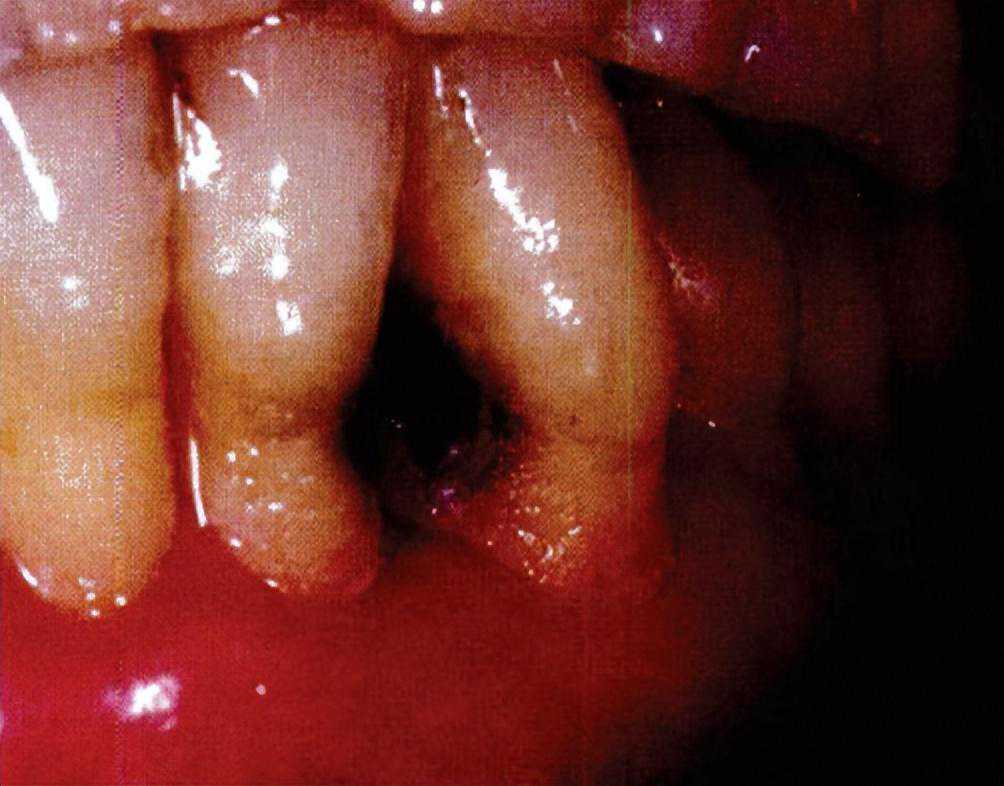

口腔健康是全身健康的重要组成部分,上海的口腔健康状况优于全国平均水平,但仍不容乐观,尤其是儿童、青少年龋患情况及预防措施。应当发挥以高水平口腔医学院校为主体、依托公立医院建设的国家口腔医学中心和国家口腔疾病临床医学研究中心的作用,以一流学科、临床资源及人才队伍优势,提升医疗、教学、科研、预防、管理“五位一体”的效能,持续推进健康口腔行动。